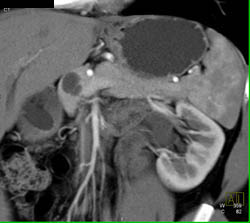

Splenic Tissue- in Tail of Pancreas